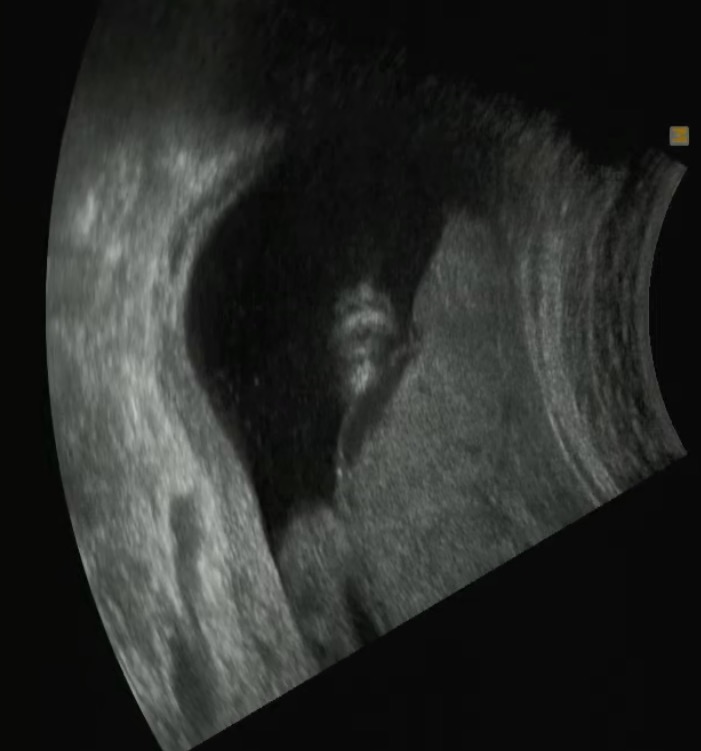

먼저 애기 초음파 먼저 봤다.

전반적으로 잘 크고 있고 정상 범위라고 함.

내 배꼽에 가려서 얼굴이 잘 보이진 않는데,

구순구개열 확인을 위해 윗입술과 콧구멍 부분을 찍어서 보여주셨는데 이게 뭐라고 귀엽다. ㅎㅎ

(남들 보기엔 공포영화의 한장면 같겠지만… )